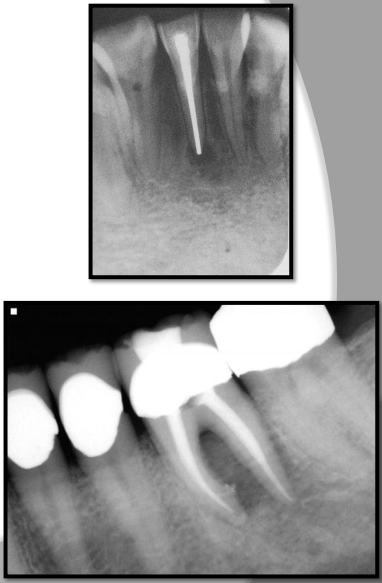

Describe root surface caries.

Involves cementum and dentin; NO ENAMEL INVOLVEMENT

Early lesions may be difficult to detect on radiograph

Typically occurs just below cervical region of the tooth

Bone loss and gingival recession must be evident

Describe the clinical and radiographic appearance of Root surface caries

Clinical → easily seen on exposed root surface; SAUCER-SHAPED; brownish colour; leathery texture

Radiographic → cupped-out or crater-shaped radiolucency; interproximal just below CEJ

T or F Root surface caries are most commonly seen on maxillary premolars and molars

FALSE - most common for MAND PM and Molars

Identify the carious lesion.Â

Root surface cariesÂ

Describe Recurrent caries

AKA Secondary caries

Evident adjacent to pre-existing restoration due to inadequate cavity prep, defective margins, or incomplete removal of caries prior to placing restoration

appears as radiolucent area just beneath restoration on radiograph.